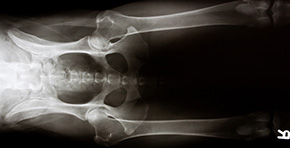

Röntgen

In der Tiermedizin dient das Röntgen zur Feststellung von Anomalien im Körper, die im Zusammenhang mit Symptomen und eventuell anderen Untersuchungen eine Diagnose ermöglichen, wie z.Bsp. Untersuchungen des Skeletts: Knochenbrüche, Tumorerkrankungen, Gelenkveränderungen, etc., Untersuchungen des Brust- und Bauchraums: Magendrehung, Blasensteine, Luft oder freie Flüssigkeit, Tumore, Organbeschaffenheit.